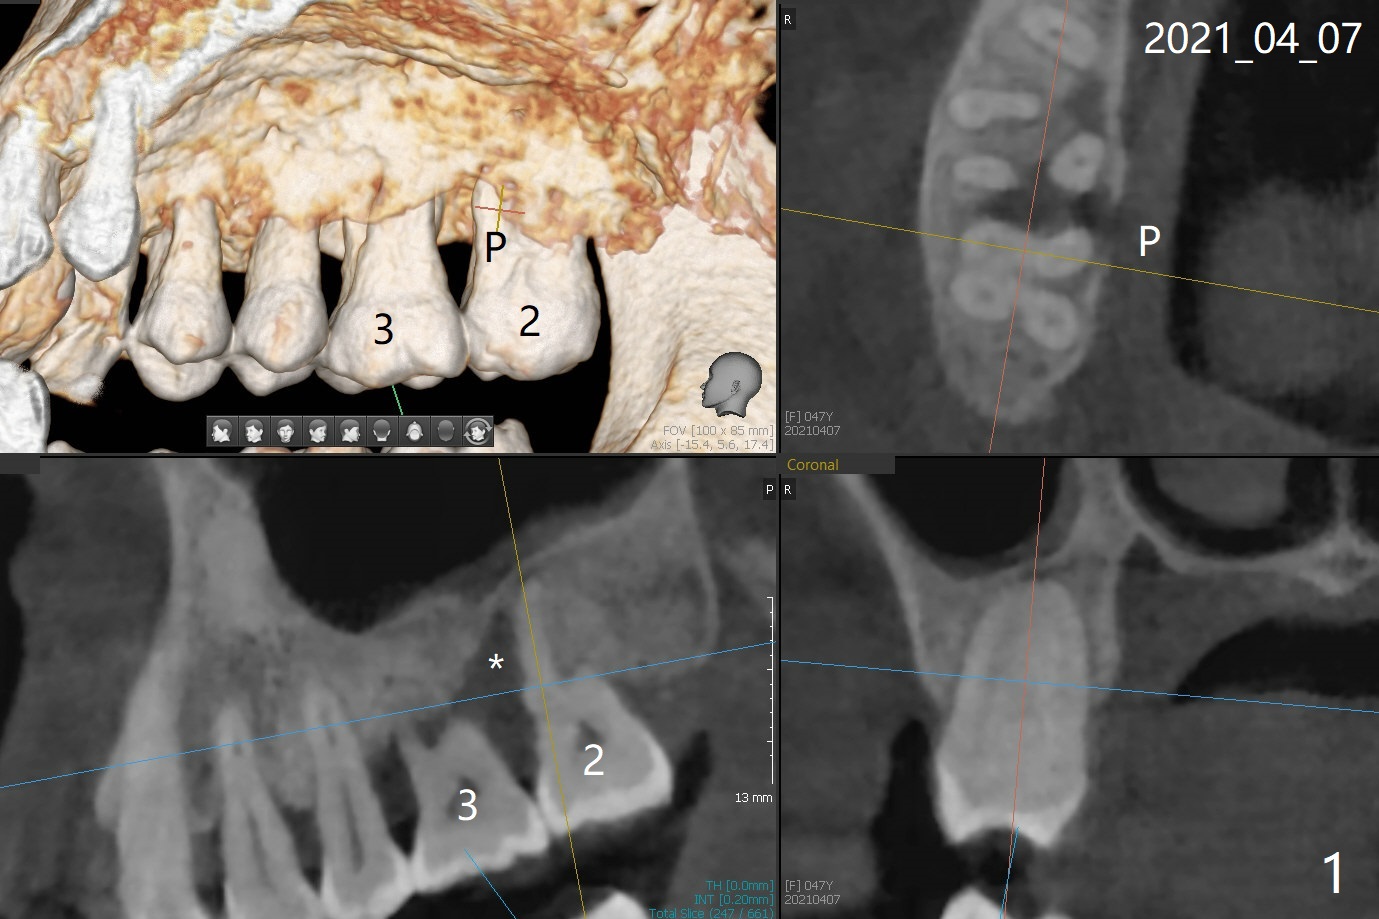

47岁女31号牙即刻种植术后一个月,2,3之间牙周炎发作(图一,二),局麻下,再次局部深些(四个月后),放置Arestin。